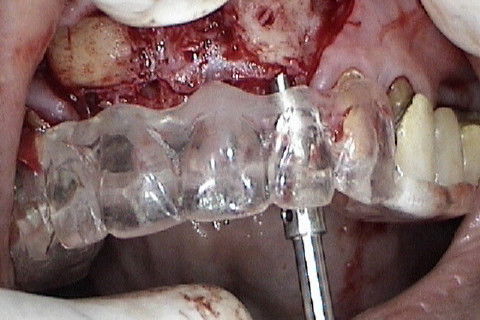

Marcação atraves do guia cirúrgico das posições dos implantes

Colocação dos implantes nas regiões 12 e 22 e perfuração das regiões 11 e 21